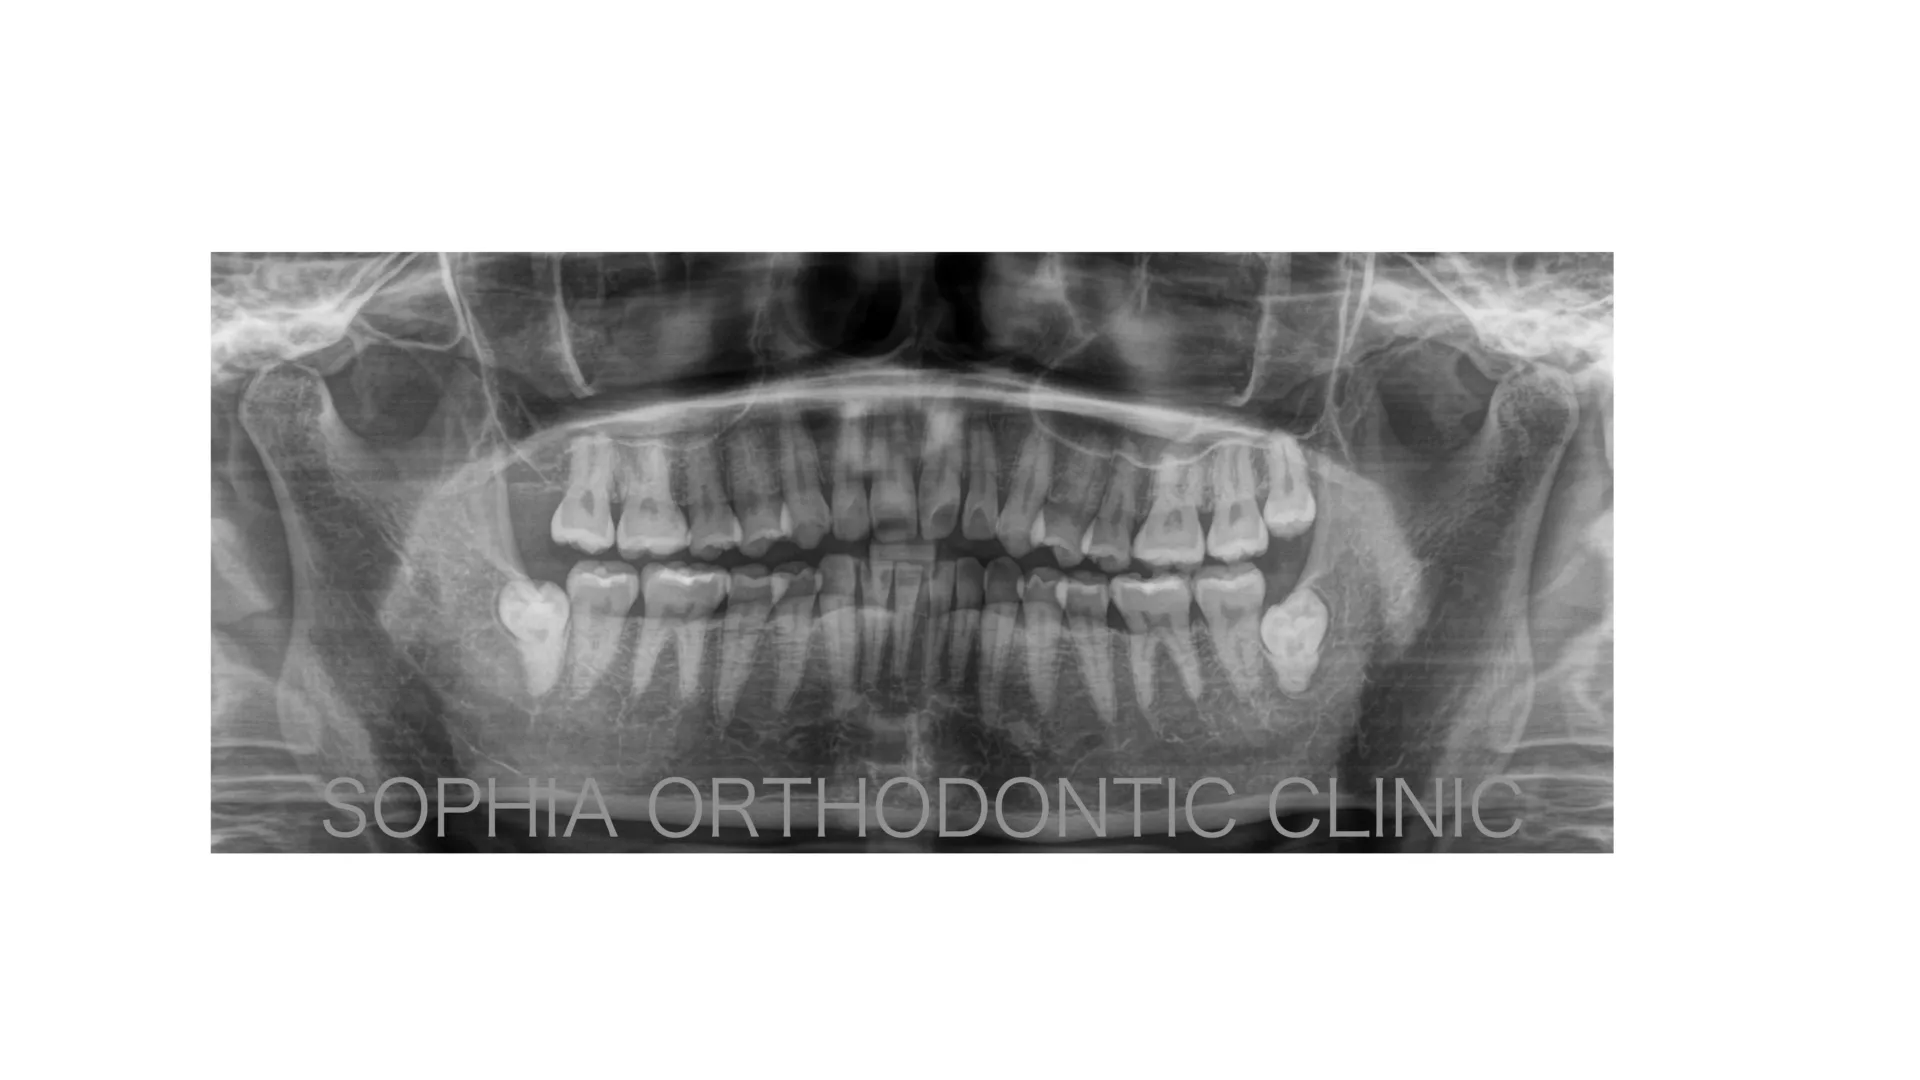

開咬症例 非抜歯 唇側